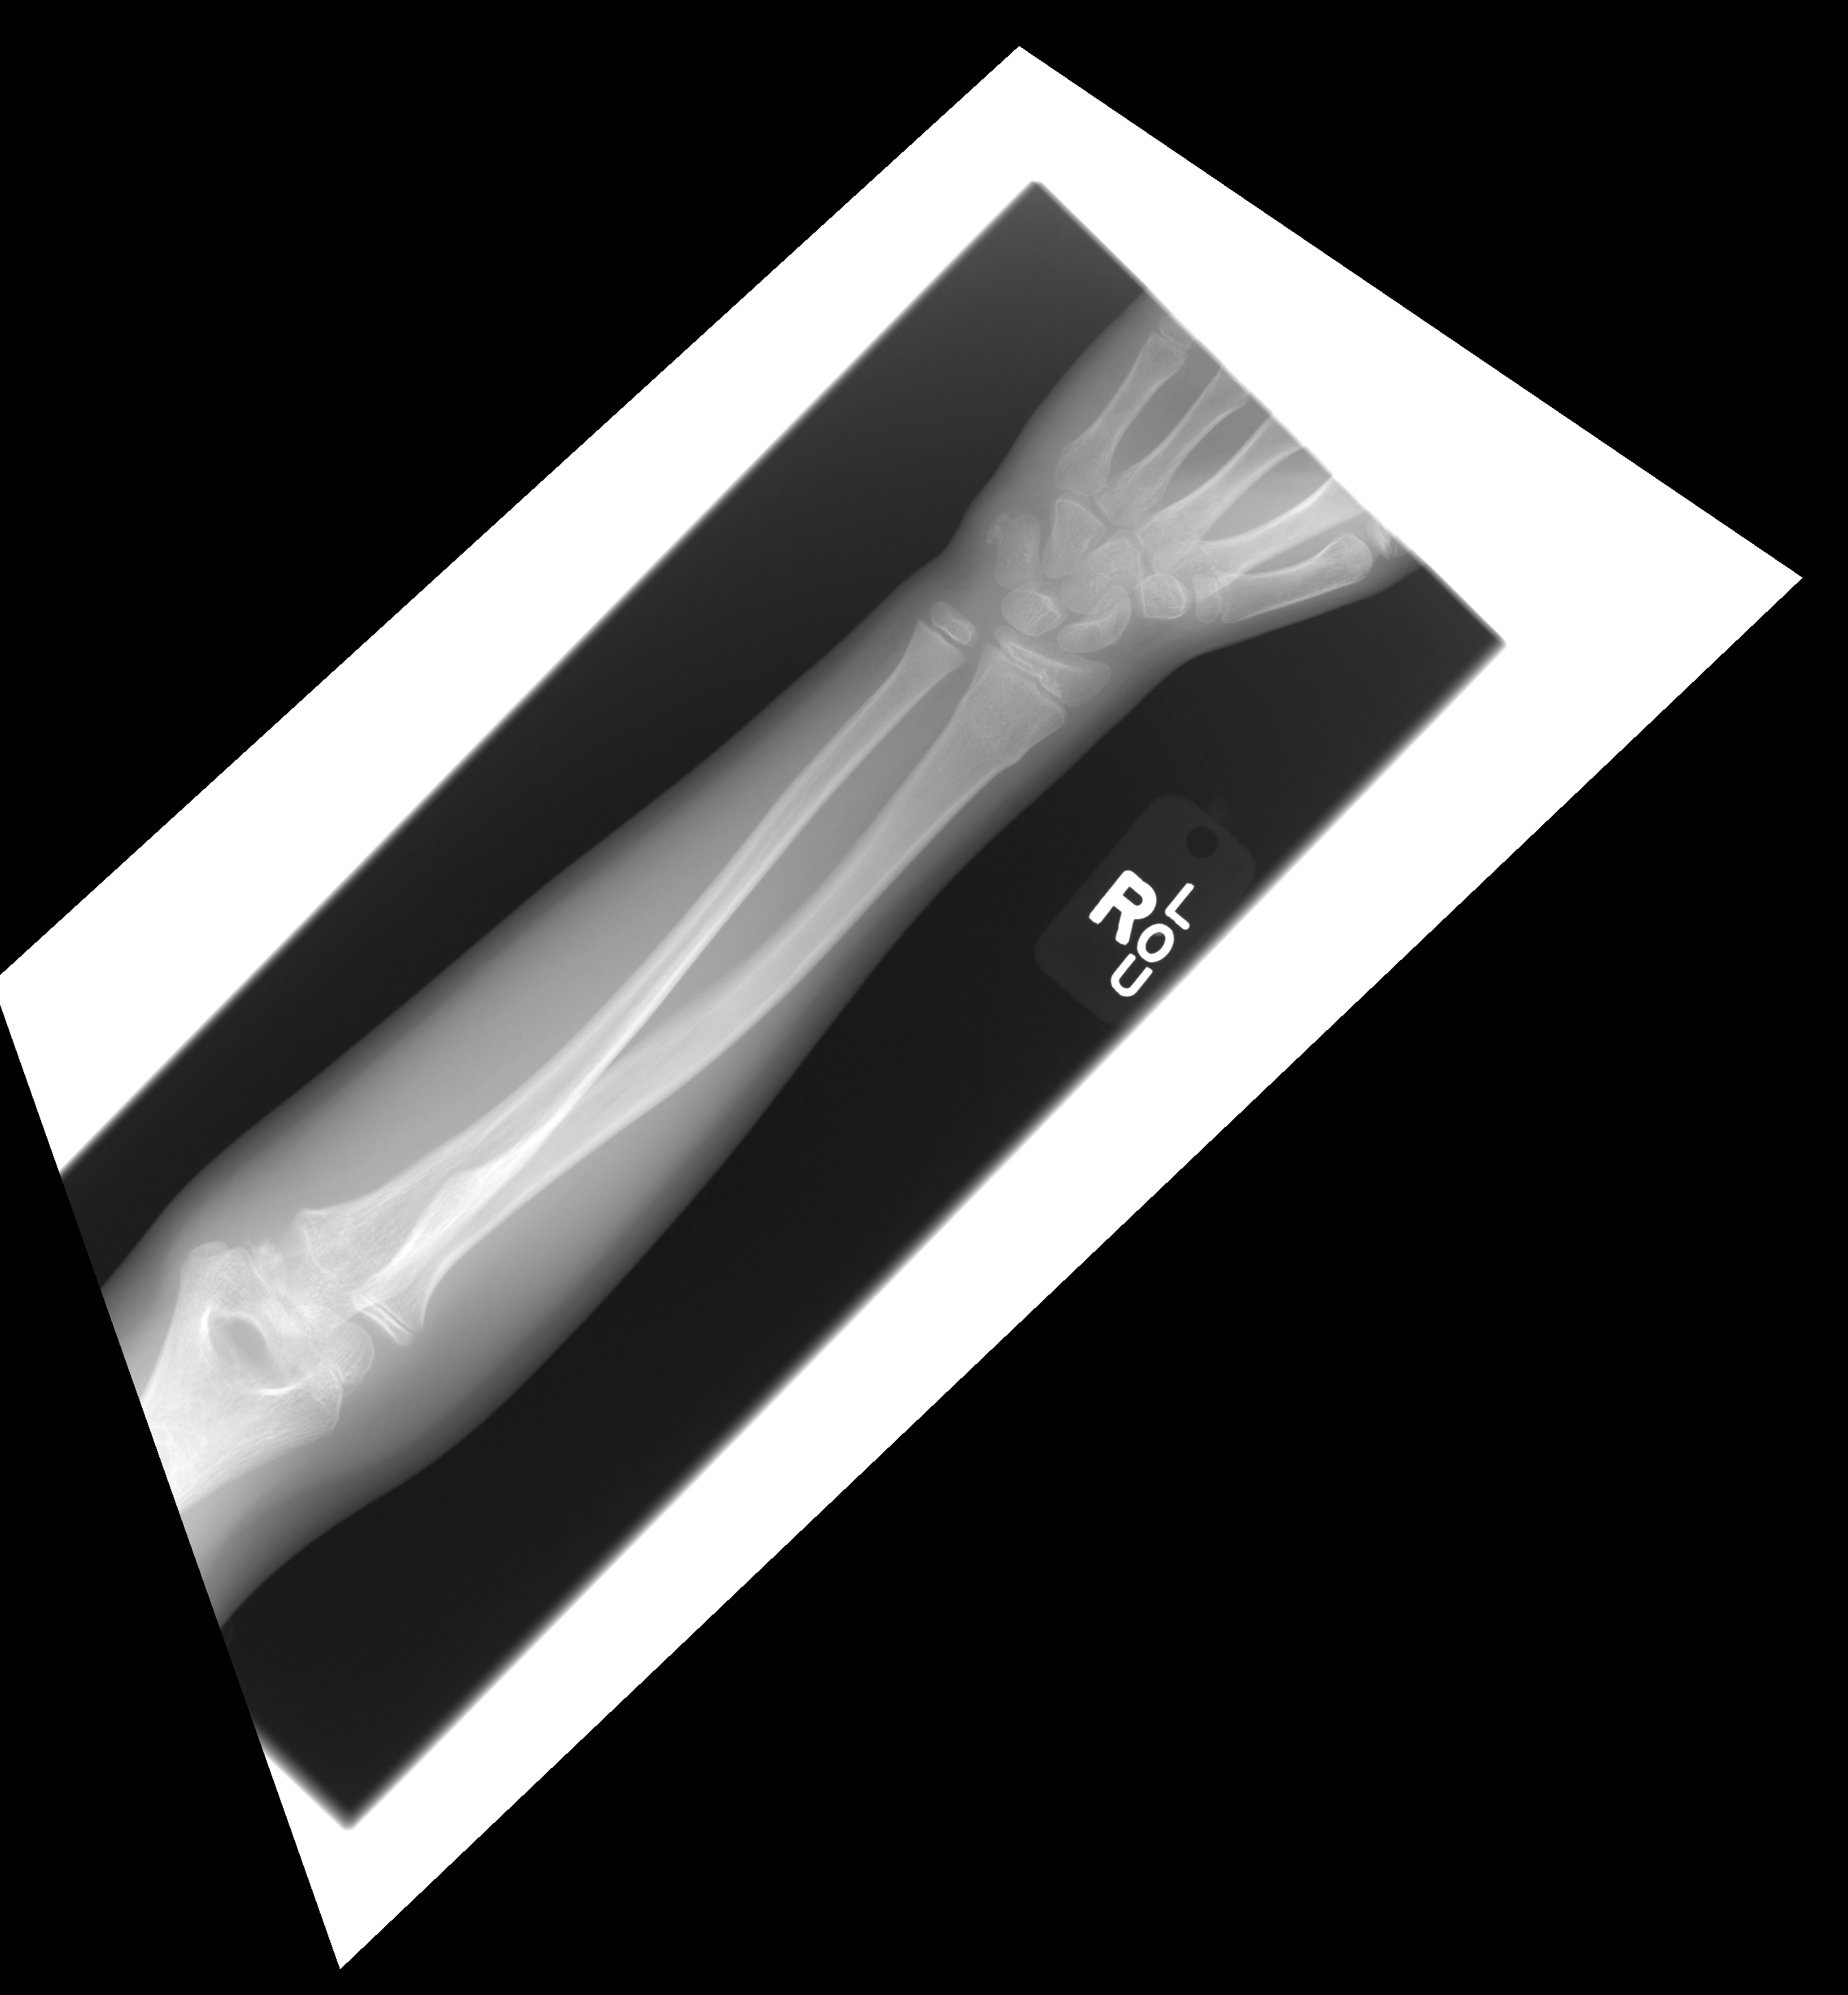

| 5 |

Abnormal dis rad |

Abnormal Right distal radius Torus fracture |

Correct |